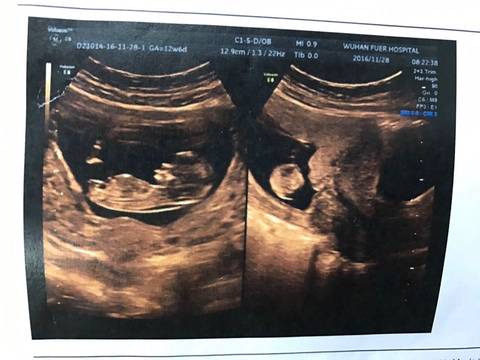

头胎。本来没想怀的。结果意外怀上了。一想家里又催,自己也快三十岁了。就放下工作好好迎接人生的另一阶段吧。但是因为是计划外的,自己很多禁忌都犯了,而且也不知道啥时候怀的。所以很紧张。做检查显示是12W+4,昨晚到早上一直超紧张!生怕有一点儿问题。上午检查结果出来,目前一切正常,心里的石头暂时落地了。接下来就是唐筛了,准备做无创NDA。有了宝宝才发现自己的母性一瞬间爆发了,好喜欢小孩子,希望一步步都顺利。

接nt顺利通过